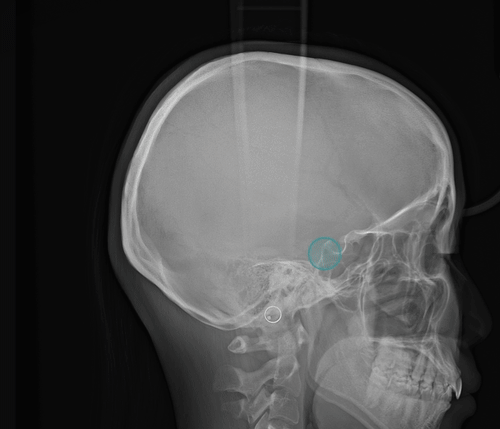

Cephalometric superimposition toggle animation

S-N Point auto registration

S-N Point plotting